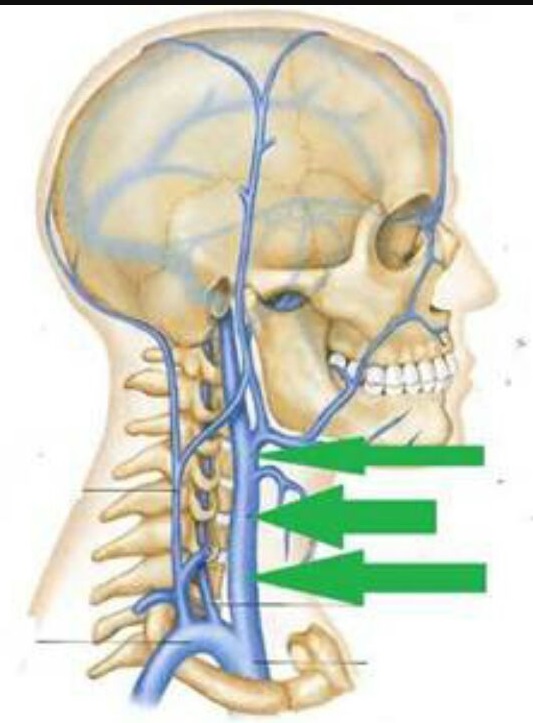

Анатомия внутренней яремной вены: КТ изображения